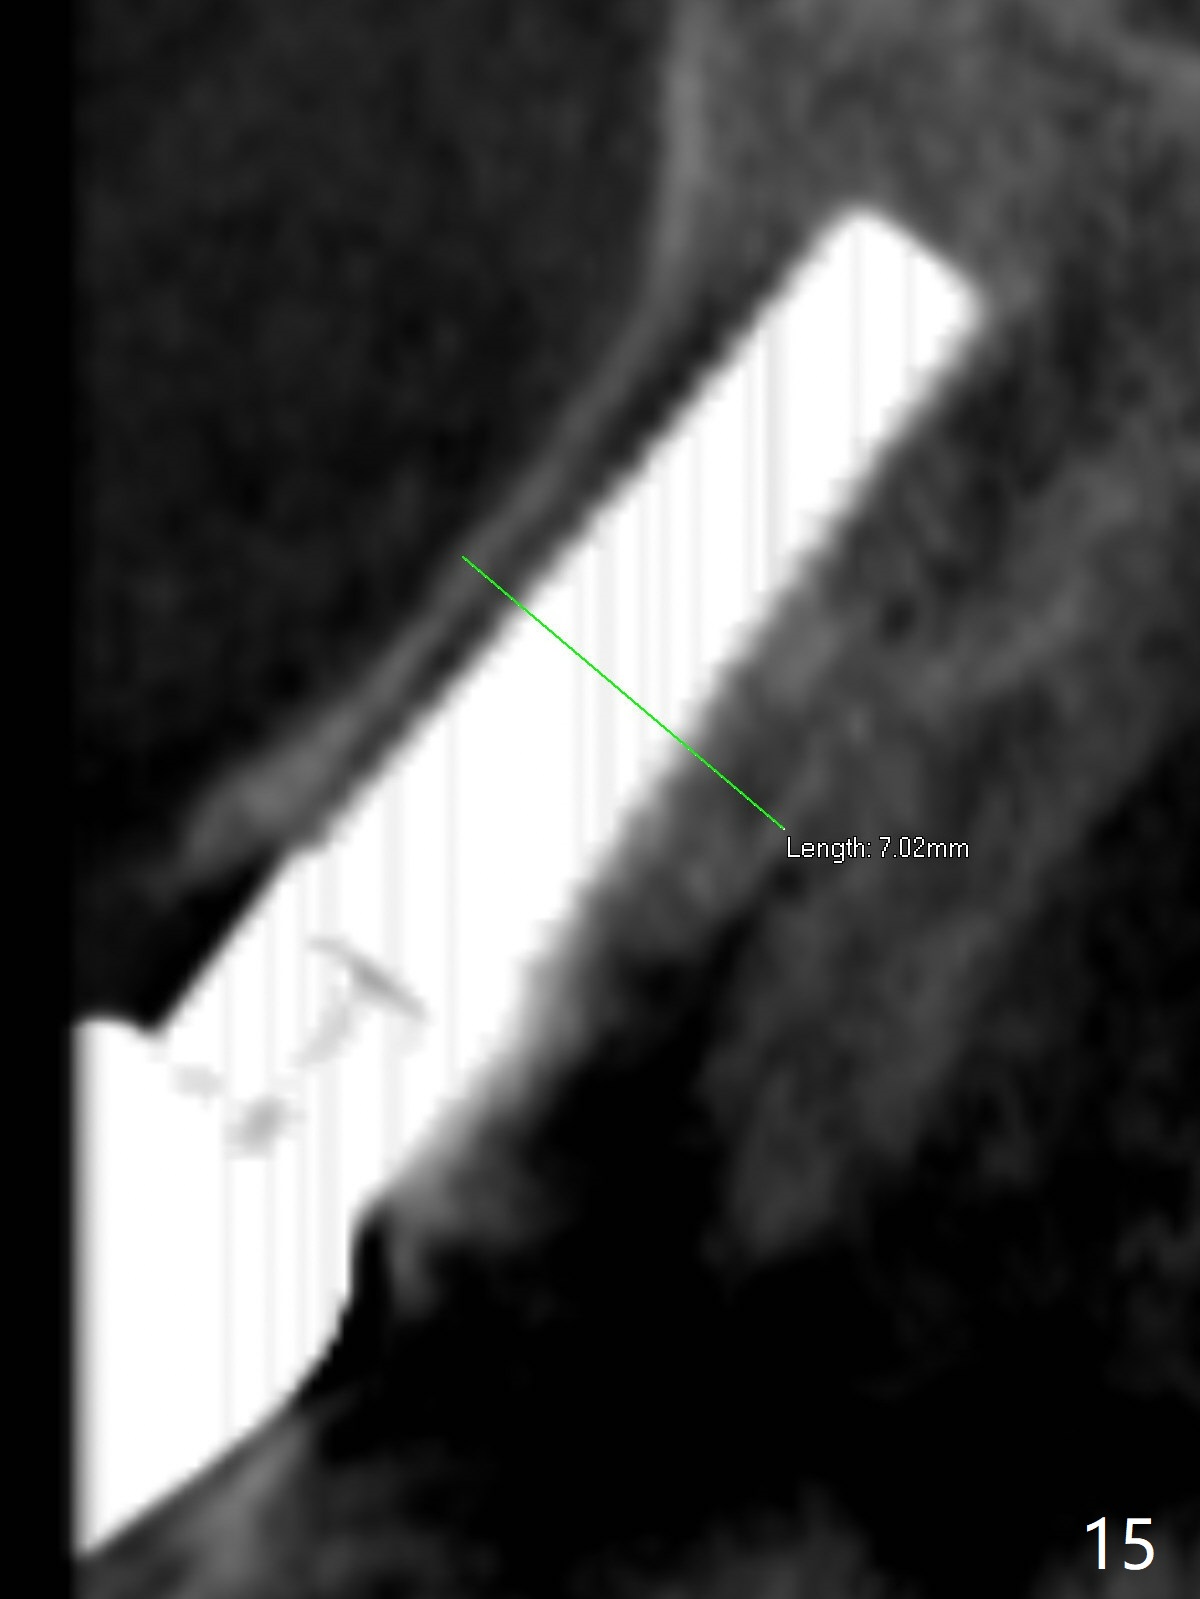

The edentulous area at #7 is narrow both buccopalatally and mesiodistally, whereas the crowns of the neighboring teeth are long (Fig.1,2). For the latter reason, it is difficult to remove the apical portion of the root, including gutta percha with surgical handpiece (Fig.3 *) for socket shield (Fig.2 *). To avoid the perspective implant touching socket shield, initial osteotomy is palatal. When a 2 mm drill is being used, the coronal end of the palatal plate starts to perforate. A 2.5x14 mm 1-piece implant is placed with 30 Ncm (Fig.4). The palatal plate is thin (Fig.5). Preop CT will help determine the position of initial osteotomy. The buccal gingiva seems to have been re-attached to the underlying alveolus and the provisional 1 month postop (Fig.6). The teeth #8 and 9 fracture (an implant is placed at #8 and bone graft at #9, while the implant at #7 is osteointegrating (Fig.7). In fact the shield is exposed without symptom. A year postop, another dental provider sends a photo of apparently hemorrhagic gingiva around #7 crown (Fig.8). A few days later with oral hygiene instruction, the gingiva around the exposed root piece is healthy (Fig.9). The root surface is reduced; with socket shield, there is no buccal plate collapse; in contrast the neighboring buccal plate (at #8 and 9) is concave (Fig.10). There is minimal exposure 11 days postop (Fig.11). The gingiva palatal to the shield is erythematous, a possible sign of periimplantitis. The socket shield at #7 appears to be fused with the buccal plate 11 months postop (Fig.12), as compared to the implant at #10 nearly 4 years postop (Fig.14). The buccopalatal widths at #7 and 10 are equivalent (Fig.13,15).